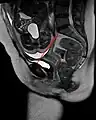

Conjugata vera as measured on sagittal MRI

Obstetric conjugate, as a measure of the pelvic inlet in the sagittal plane